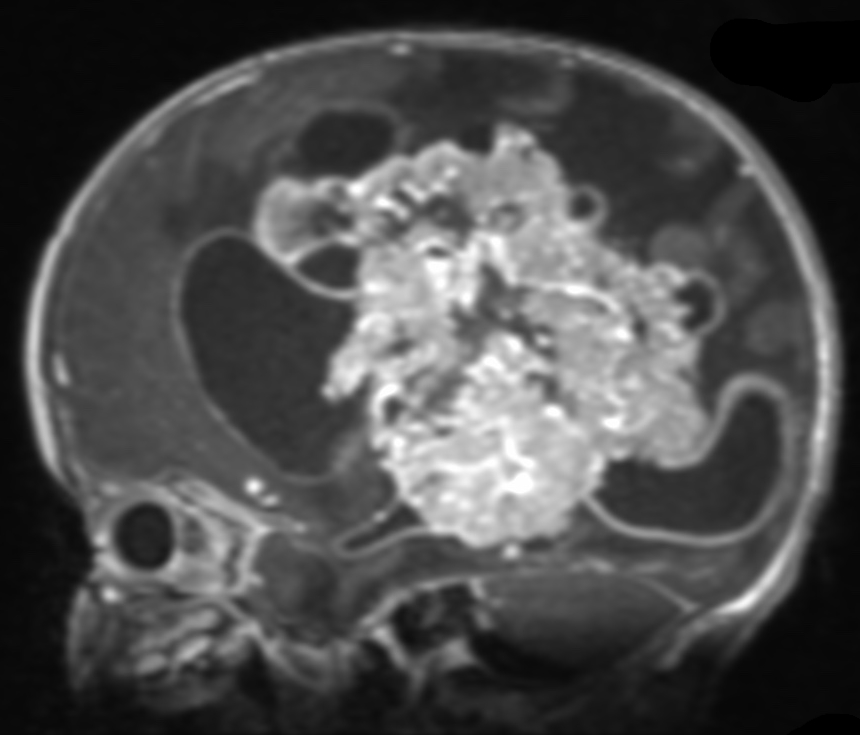

Choroid plexus tumors arise from the choroid plexus within the ventricles of the brain. These tumors are rare, representing only about 3% of brain tumors in children. About 10-20% of brain tumors found in the first year of life are choroid plexus tumors. The majority of choroid plexus tumors are either choroid plexus papillomas (CPP) or choroid plexus carcinomas (CPC). CPPs are benign and far more common, accounting for 80-90% of choroid plexus tumors. CPCs are malignant, and are more likely to spread to other parts of the brain and spinal cord. Symptoms for these tumors include headaches, nausea, lethargy, irritability, problems with development, and enlarged fontanelles. All of these are a direct result of the increased intracranial pressure and of the hydrocephalus that may be caused by the tumor. Surgical resection is the mainstay of treatment, but can be particularly complex in these cases, and should be performed by an experienced pediatric neurosurgery team.